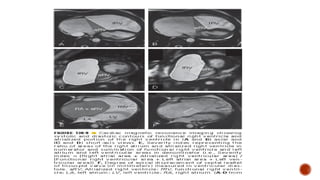

CARDIAC MRI

 Quantitative measurement of RA & RV size & systolic function

 Axial imaging provides most reliable volume of atrialized RV

 Detailed visualization of pathological anatomy (3D images)

 Technique for precise volumetric analysis of ventricular function and

intracardiac blood flow, without any geometric assumptions

 CMR delayed contrast enhancement image is a potential tool to

recognize areas of right ventricle dysplasia

The following acquisitions were performed parallel to the long axis of

the heart (horizontal and vertical long-axis planes) & perpendicular to it

(short-axis planes)

1. Balanced SSFP ( b-SSFP= steady-state free precession) sequences

using retrospective ECG gating & parallel imaging technique with an

acceleration factor of two and reconstruction algorithm GRAPPA

(generalized auto calibrating partially parallel acquisition)

2. Dark-blood techniques, being the single-shot inversion-recovery fast

SE sequence with breath holding the most commonly used

3. Phase contrast velocity map of the aorta and pulmonary arteries

4. At last delayed contrast enhanced images performed ten minutes

after injection of gadolinium-DTPA using a segmented inversion-

recovery spoiled GRE sequence